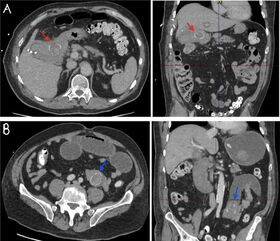

Sjö dögum eftir bráðaaðgerð fær hann kröftuga blæðingu um endaþarm og yfirlið. Ekki þreifast púls og hafin var endurlífgun. Hann varð fljótlega stöðugur og með meðvitund og púls sást við fyrstu taktgreiningu. Í framhaldi var hann fluttur á gjörgæslu með tilheyrandi stuðningsmeðferð. Gerð var ný tölvusneiðmynd sem sýndi vel afmarkaðan 11 mm æðagúl í gallblöðruslagæð (cystica), grein frá hægri lifrarslagæð (hepatica dexter). Gerð var æðaþræðing (mynd 2) og æðastíflun (embolisation) af inngripsröntgenlæknum.

Mynd 2. Æðaþræðingarmyndataka, hér sést æðagúll í gallblöðruslagæð (ör).